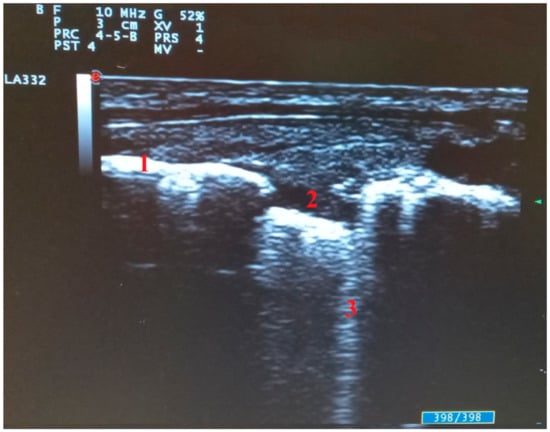

- Di Serafino, M.; Notaro, M.; Rea, G.; Iacobellis, F.; Paoli, V.D.; Acampora, C.; Ianniello, S.; Brunese, L.; Romano, L.; Vallone, G. The lung ultrasound: Facts or artifacts? In the era of COVID-19 outbreak. Radiol. Med. 2020, 125, 738–753. [Google Scholar] [CrossRef] [PubMed]